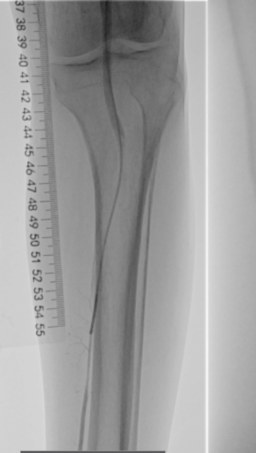

术前下肢动脉CTA提示:左下肢股、腘动脉长段闭塞,膝下动脉主干未见显影,可见少量侧支血流。

1.穿刺右侧股总动脉,“翻山”至对侧股总动脉,造影:股浅、股深动脉、腘动脉完全闭塞,膝下可见少量侧支动脉代偿。

▲患者术中即时造影显示股浅、股深动脉完全栓塞